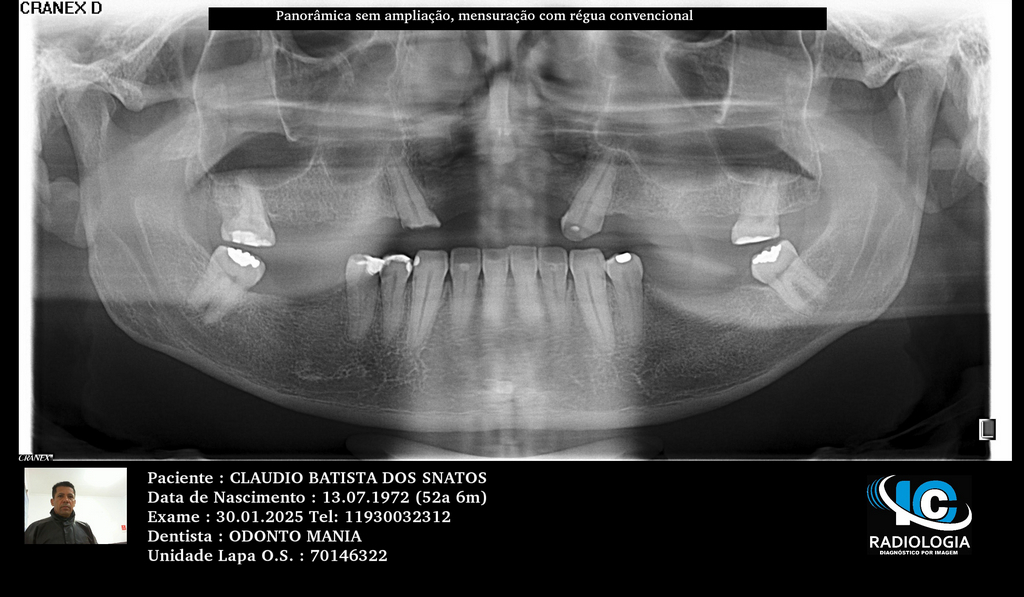

PRÓTESE TOTAL FIXA EM IMPLANTES

C.B.D.S.